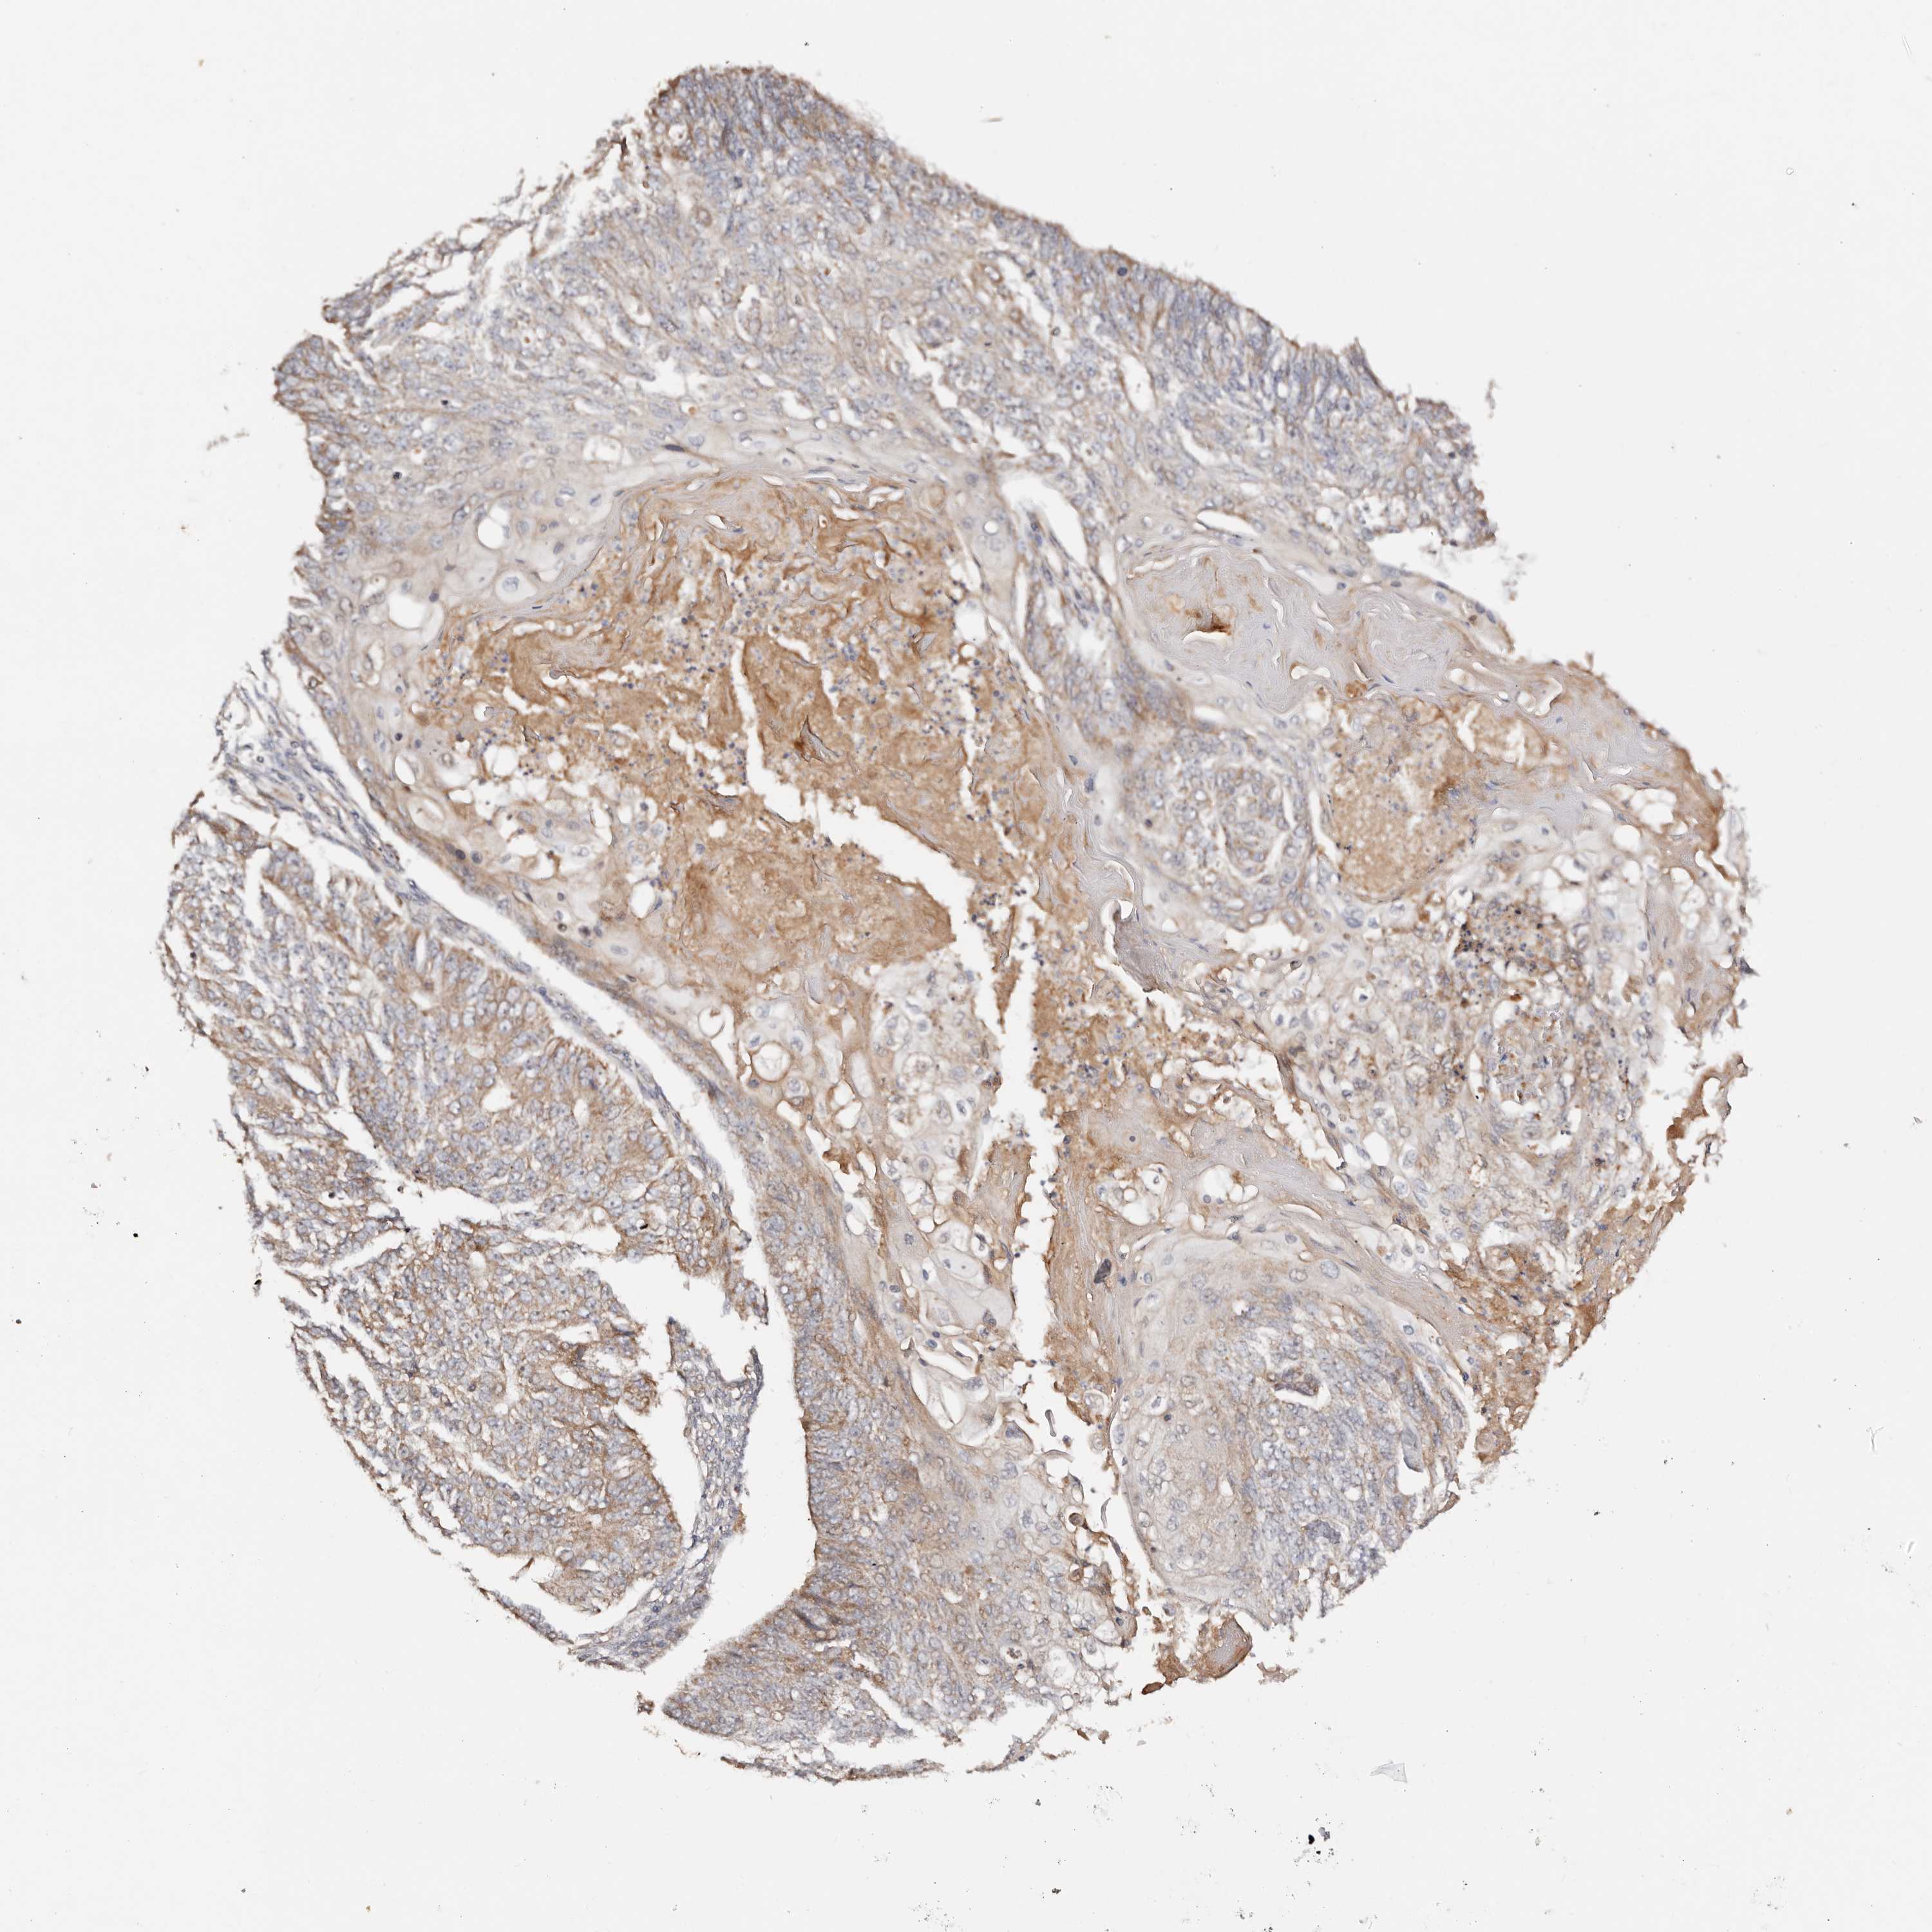

ENDOMETRIAL CANCER - Protein expressioni

A mouse-over function shows sample information and annotation data. Click on an image to view it in a full screen mode. Samples can be filtered based on level of antibody staining by selecting one or several of the following categories: high, medium, low and not detected. The assay and annotation is described here.

Note that samples used for immunohistochemistry by the Human Protein Atlas do not correspond to samples in the TCGA dataset.

Antibody stainingi

Antibody staining in the annotated cell types in the current human tissue is reported as not detected, low, medium, or high, based on conventional immunohistochemistry profiling in selected tissues. This score is based on the combination of the staining intensity and fraction of stained cells.

Each image is clickable and will lead to virtual microscopy that enables deeper exploration of all samples and also displays staining intensity scores, fraction scores and subcellular localization as well as patient and tissue information for each sample.

Antibody HPA029467

Staining

High

Medium

Low

Not detected

Intensity

Strong

Moderate

Weak

Negative

Quantity

>75%

75%-25%

<25%

None

Location

Nuclear

Cytoplasmic/membranous

Cytoplasmic/membranous,nuclear

Adenocarcinoma, NOS

Adenocarcinoma, metastatic, NOS